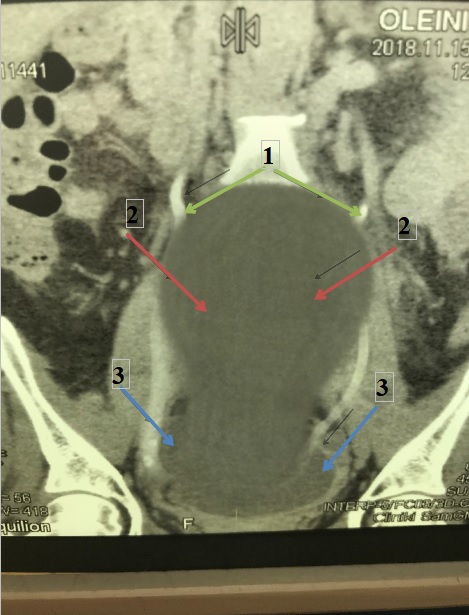

При этом функция обеих почек была сохранена, полостная система не расширена (рисунок 2). Четких данных, указывающих на локализацию дефекта мочевыводящих путей, не обнаружено. Учитывая данные КТ и локализации предыдущей операции, установлен диагноз «перфорация нижней трети правого мочеточника?, забрюшинный мочевой затек».

Рисунок 2. Фронтальная проекция. Компьютерная томограмма с контрастом. В мочеточниках с обеих сторон отмечается наличие контраста (1). Мочевой затек (2). Мочевой пузырь (3).

Figure 2. Frontal projection. Contrast-enhanced computer tomogram. The presence of contrast is noted in the ureters on both sides (1). Extravasation of urine (2). Urinary bladder (3).